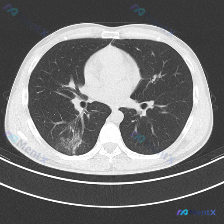

一张胸部CT肺窗图的结节分析,重点在右肺磨玻璃样病灶

看到一张胸部CT肺窗的图像,整理了一下分析思路,和大家分享讨论。 首先看影像质量和解剖定位:图像是肺窗横断面,主动脉弓上方或水平层面,质量不错,无明显伪影,能清晰看肺实质。 然后重点是肺部结构,右肺上野有微小结节,还有个磨玻璃结节(GGO),内部密度不均,边缘不算锐利。左肺相对清晰,气道和肺纹理基本...